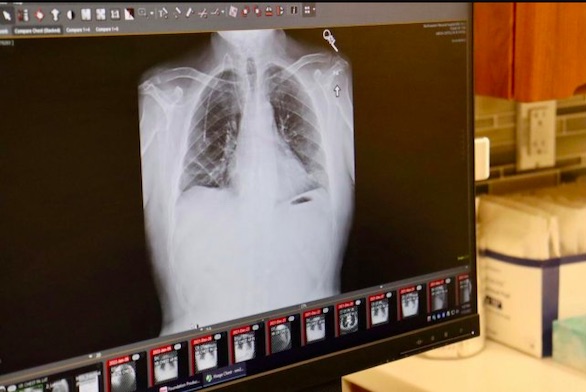

مدار الساعة -أعلن أطباء في مستشفى نورث وسترن ميديسن، بمدينة شيكاغو الأمريكية، بأنهم أجروا عملية هي الأولى من نوعها تم خلالها زرع رئتين بنجاح لمريض مصاب بسرطان الرئة.

وقال مسؤولو المستشفى، إن المريض ألبرت كوري (54 عاماً) من شيكاغو، لم يكن مدخناً، وتم تشخيص إصابته بسرطان الرئة في بداية جائحة كورونا.من جهته قال الدكتور أنيكت بهارات، وهو أحد الجراحين الذين أجروا العملية ورئيس قسم جراحة الصدر في المستشفى، في بيان صحفي: " بالنسبة للمرضى الذين يعانون من سرطان الرئتين في المرحلة الرابعة، فإن عملية زراعة الرئة غير ممكنة، ولكن لحسن حظ ألبرت أن السرطان كان محصوراً في صدره، وكنا واثقين من قدرتنا على التخلص من السرطان أثناء الجراحة وإنقاذ حياته”على الرغم من أن عمليات زرع الرئة أصبحت أكثر شيوعًا لدى الأشخاص المصابين بالنوع المميت من السرطان، إلا أن إجراءها اقتصر على الأشخاص الذين لم يصلوا بعد إلى المرحلة الرابعة من السرطان، حيث تنتشر الأورام في الرئتين وأعضاء أخرى من الجسم، ولكن في حالة ألبرت فكان الوضع مختلفاً حيث اقتصرت الأورام على صدره رغم وصول المرض إلى المرحلة الرابعة.وقال ألبرت الذي كان يعمل في وزارة النقل بمدينة شيكاغو، إنه أصيب لأول مرة بآلام الظهر وعانى من نوبات من العطس والقشعريرة والسعال مع المخاط في أوائل عام 2020. في البداية اعتقد بأنه مصاب بعدوى كورونا، لكنه بدأ بعد ذلك يسعل الدم واتصل بطبيب الرعاية الأولية.عندما زار الطبيب، اكتشف أنه مصاب بسرطان الرئة في المرحلة الأولى، لكن بسبب جائحة كورونا، لم يتمكن من بدء العلاج على الفور. وفي غضون بضعة أشهر، تقدم مرض السرطان لديه إلى المرحلة الرابعة، وأخبره الأطباء أنه لا يملك فرصة للبقاء على قيد الحياة.بعد ذلك شاهد تقريراً إخبارياً عن عمليات زرع الرئة في قناة تلفزيونية، وحدد موعداً لمعرفة ما إذا كان مؤهلاً لإجراء عملية زرع رئتين.والتقى ألبرت بالدكتور يونغ تشاي، أخصائي الأورام الطبي في مركز لوري للسرطان في نورث وسترن ميديسن، والذي أراد تجربة خيارات العلاج الأخرى قبل التفكير في زراعة الرئة.ومع ذلك، استمرت صحة ألبرت في التدهور، وانتهى به المطاف في وحدة العناية المركزة على جهاز التنفس الصناعي مع التهاب رئوي وتعفن الدم، مما دفع الأطباء لإجراء تقييم لحالته، وتبين بأنه مؤهل للحصول على رئتين جديدتين لأن الورم كان موضعياً في الصدر ولم ينتشر إلى أجزاء أخرى من جسده وهو أمر نادر الحدوث في المرحلة الرابعة من السرطان.حصل ألبرت على رئتيه الجديدتين في 25 سبتمبر، وبعد ستة أشهر من العملية، لم يعد بحاجة إلى دعم الأكسجين للتنفس و بدأ بممارسة حياته بشكل طبيعي.يتم تشخيص ما يقرب من 250.000 شخص في الولايات المتحدة بسرطان الرئة سنويًا، ويموت أكثر من 130.000 بسبب المرض كل عام، وفقًا لتقديرات جمعية السرطان الأمريكية. ويُعد سرطان الرئة السبب الرئيسي للوفيات المرتبطة بالسرطان في الولايات المتحدة، ويشكل ما يقرب من 25٪ من هذه الوفيات، وفق ما نقل موقع “يو بي آي” الإلكتروني.عملية زرع رئتين مزدوجة تنقذ حياة أمريكي مصاب بسرطان الرئة